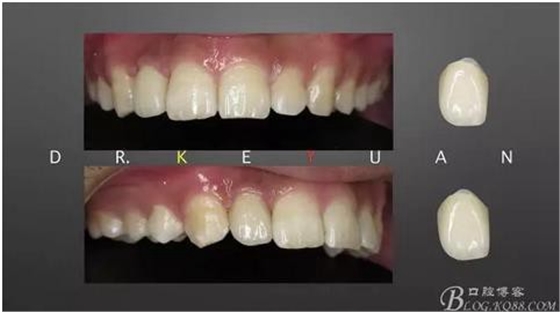

11、牙齦狀況對(duì)比(有時(shí)候你把患者約的時(shí)間太長,他可能會(huì)不理解你,約著約著就再也約不過來了,有些時(shí)候患者的修復(fù)熱情和臨床的治療程序可能成反比,我們要做金玉其外、金玉其中的修復(fù),實(shí)難取舍)

12、粘接后即刻(齦緣的高度略有差異,這應(yīng)該可以說明冠延長術(shù)和正畸牽引的效果差異)

13、術(shù)前術(shù)后對(duì)比